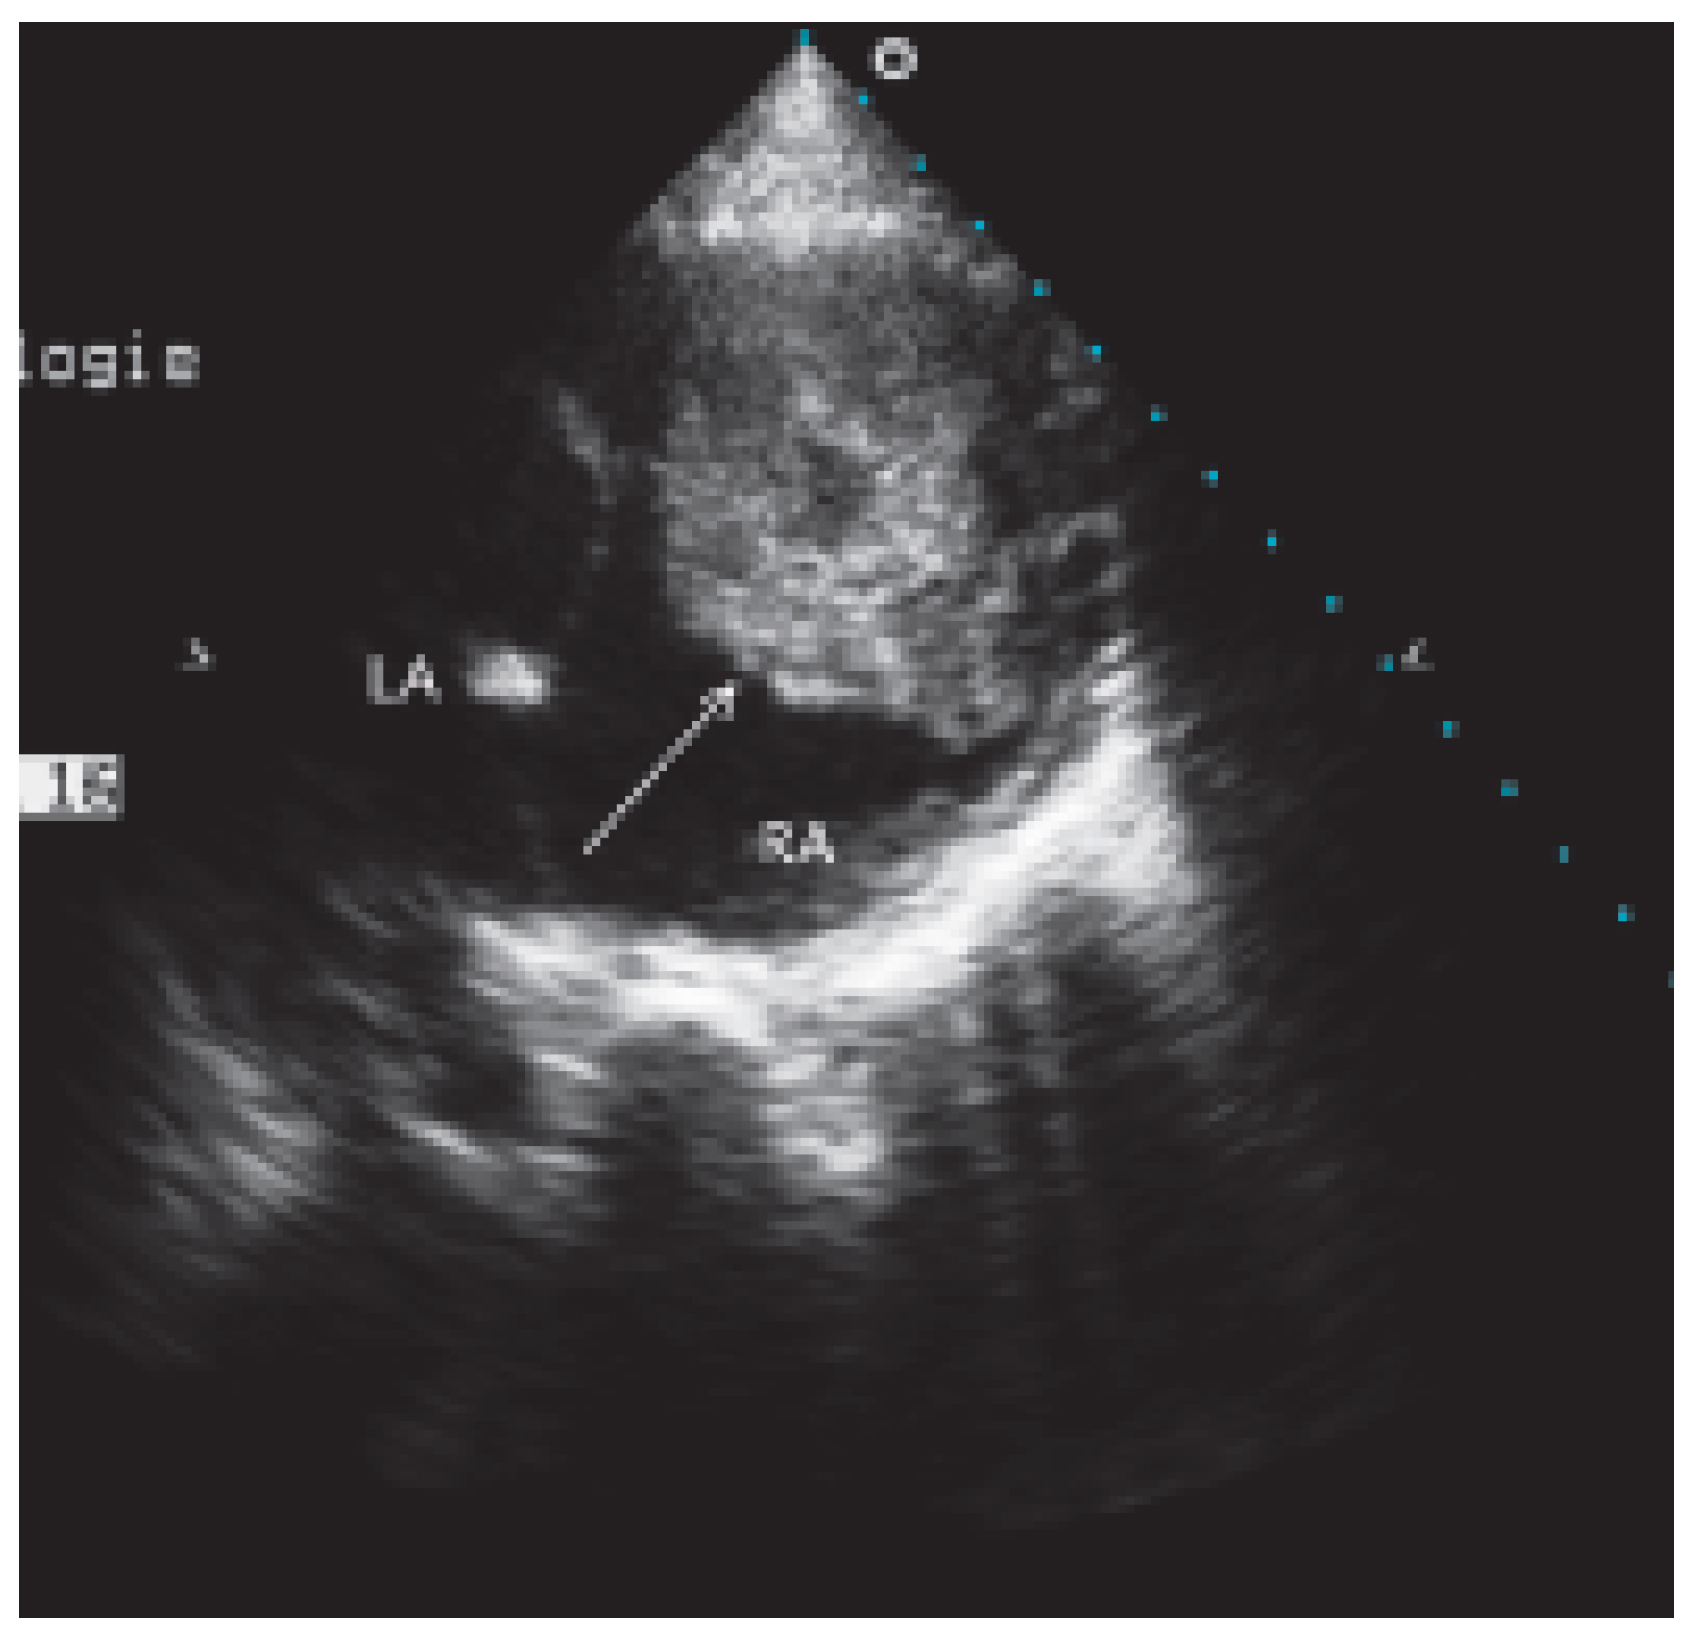

Case report